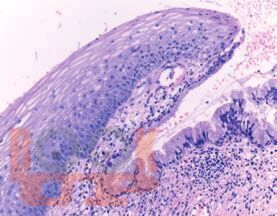

Основы клинической цитологии

В книге показаны значимость и возможности метода клинической цитологии в современной клинической практике; приведены правила и особенности технологии выполнения цитологического исследования; представлены основы и принципы цитологической диагностики и формирования морфологического диагноза. Предложены пути совершенствования и повышения эффективности цитологической диагностики для решения основной задачи в борьбе с онкологическими заболеваниями — достичь высоких и стабильных показателей в ранней и точной диагностике злокачественных новообразований.

Книга предназначена для врачей — клинических цитологов и специалистов, работающих в области клинической цитологии, врачей-клиницистов, принимающих участие в выполнении цитологического исследования и использующих методы цитологического анализа в клинической практике (эндоскопистов, онкологов, хирургов, гинекологов, эндокринологов и др.). Книга может представлять интерес для организаторов здравоохранения, решающих задачи по повышению эффективности и качества оказания медицинской помощи населению в борьбе с онкологическими заболеваниями.